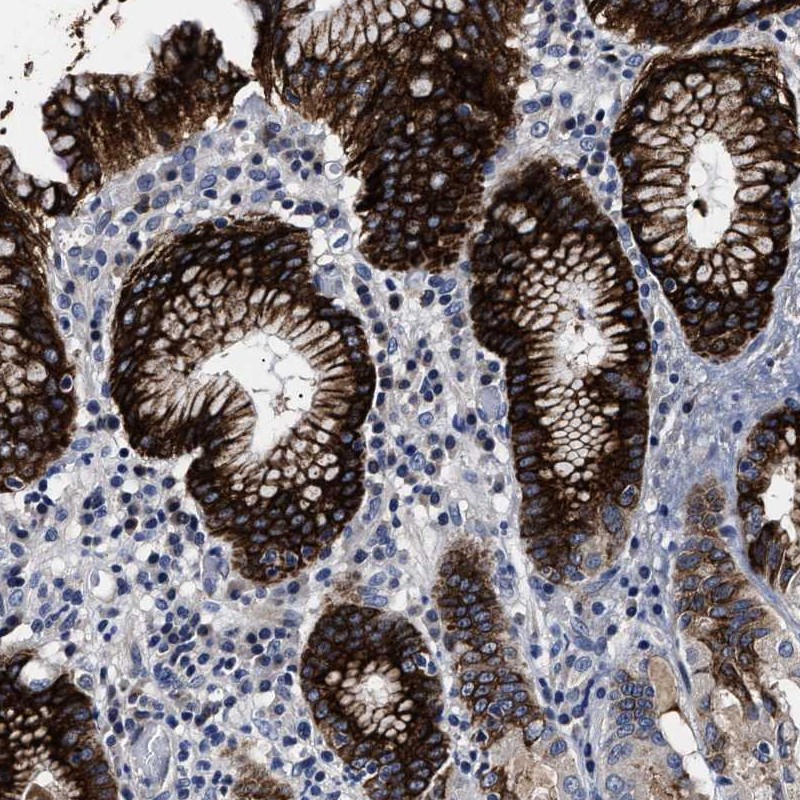

Immunohistochemical staining of human stomach shows strong positivity in the gastric pits.